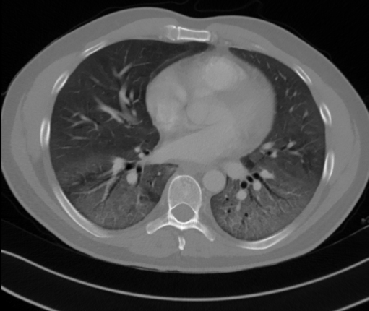

Figure 1 shows four CT scan slices, two from a non-COVID-19 CT scan, on the left and two from a COVID-19 scan, on the right. Bilateral ground glass regions are seen especially in lower lung lobes in the COVID-19 slices.